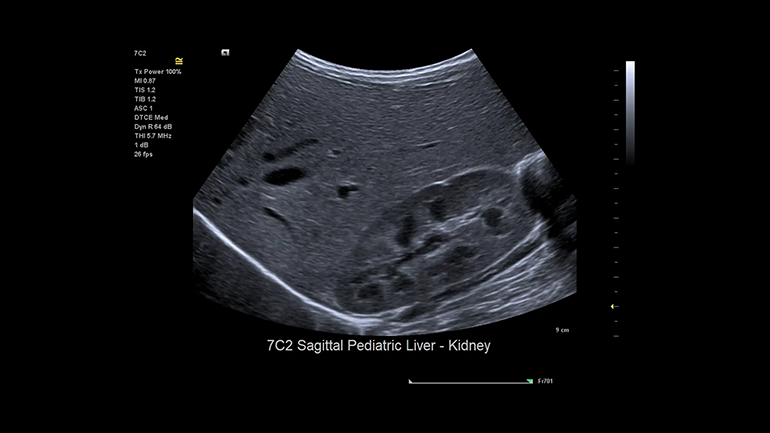

B-режим. Высокое контрастное разрешение и однородность изображений — отличное диагностическое качество.

B-режим. Высокое контрастное разрешение и однородность изображений — отличное диагностическое качество. Цветовые допплеровские режимы. Надежность диагностики повышается благодаря высокочувствительному цветовому доплеровскому режиму при снижении артефактов яркости цвета.